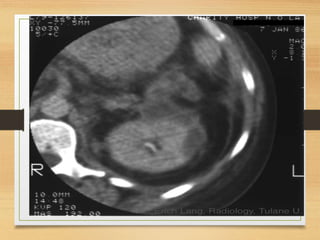

CASE 4

• A 64-year-old man presents with a 2-month history